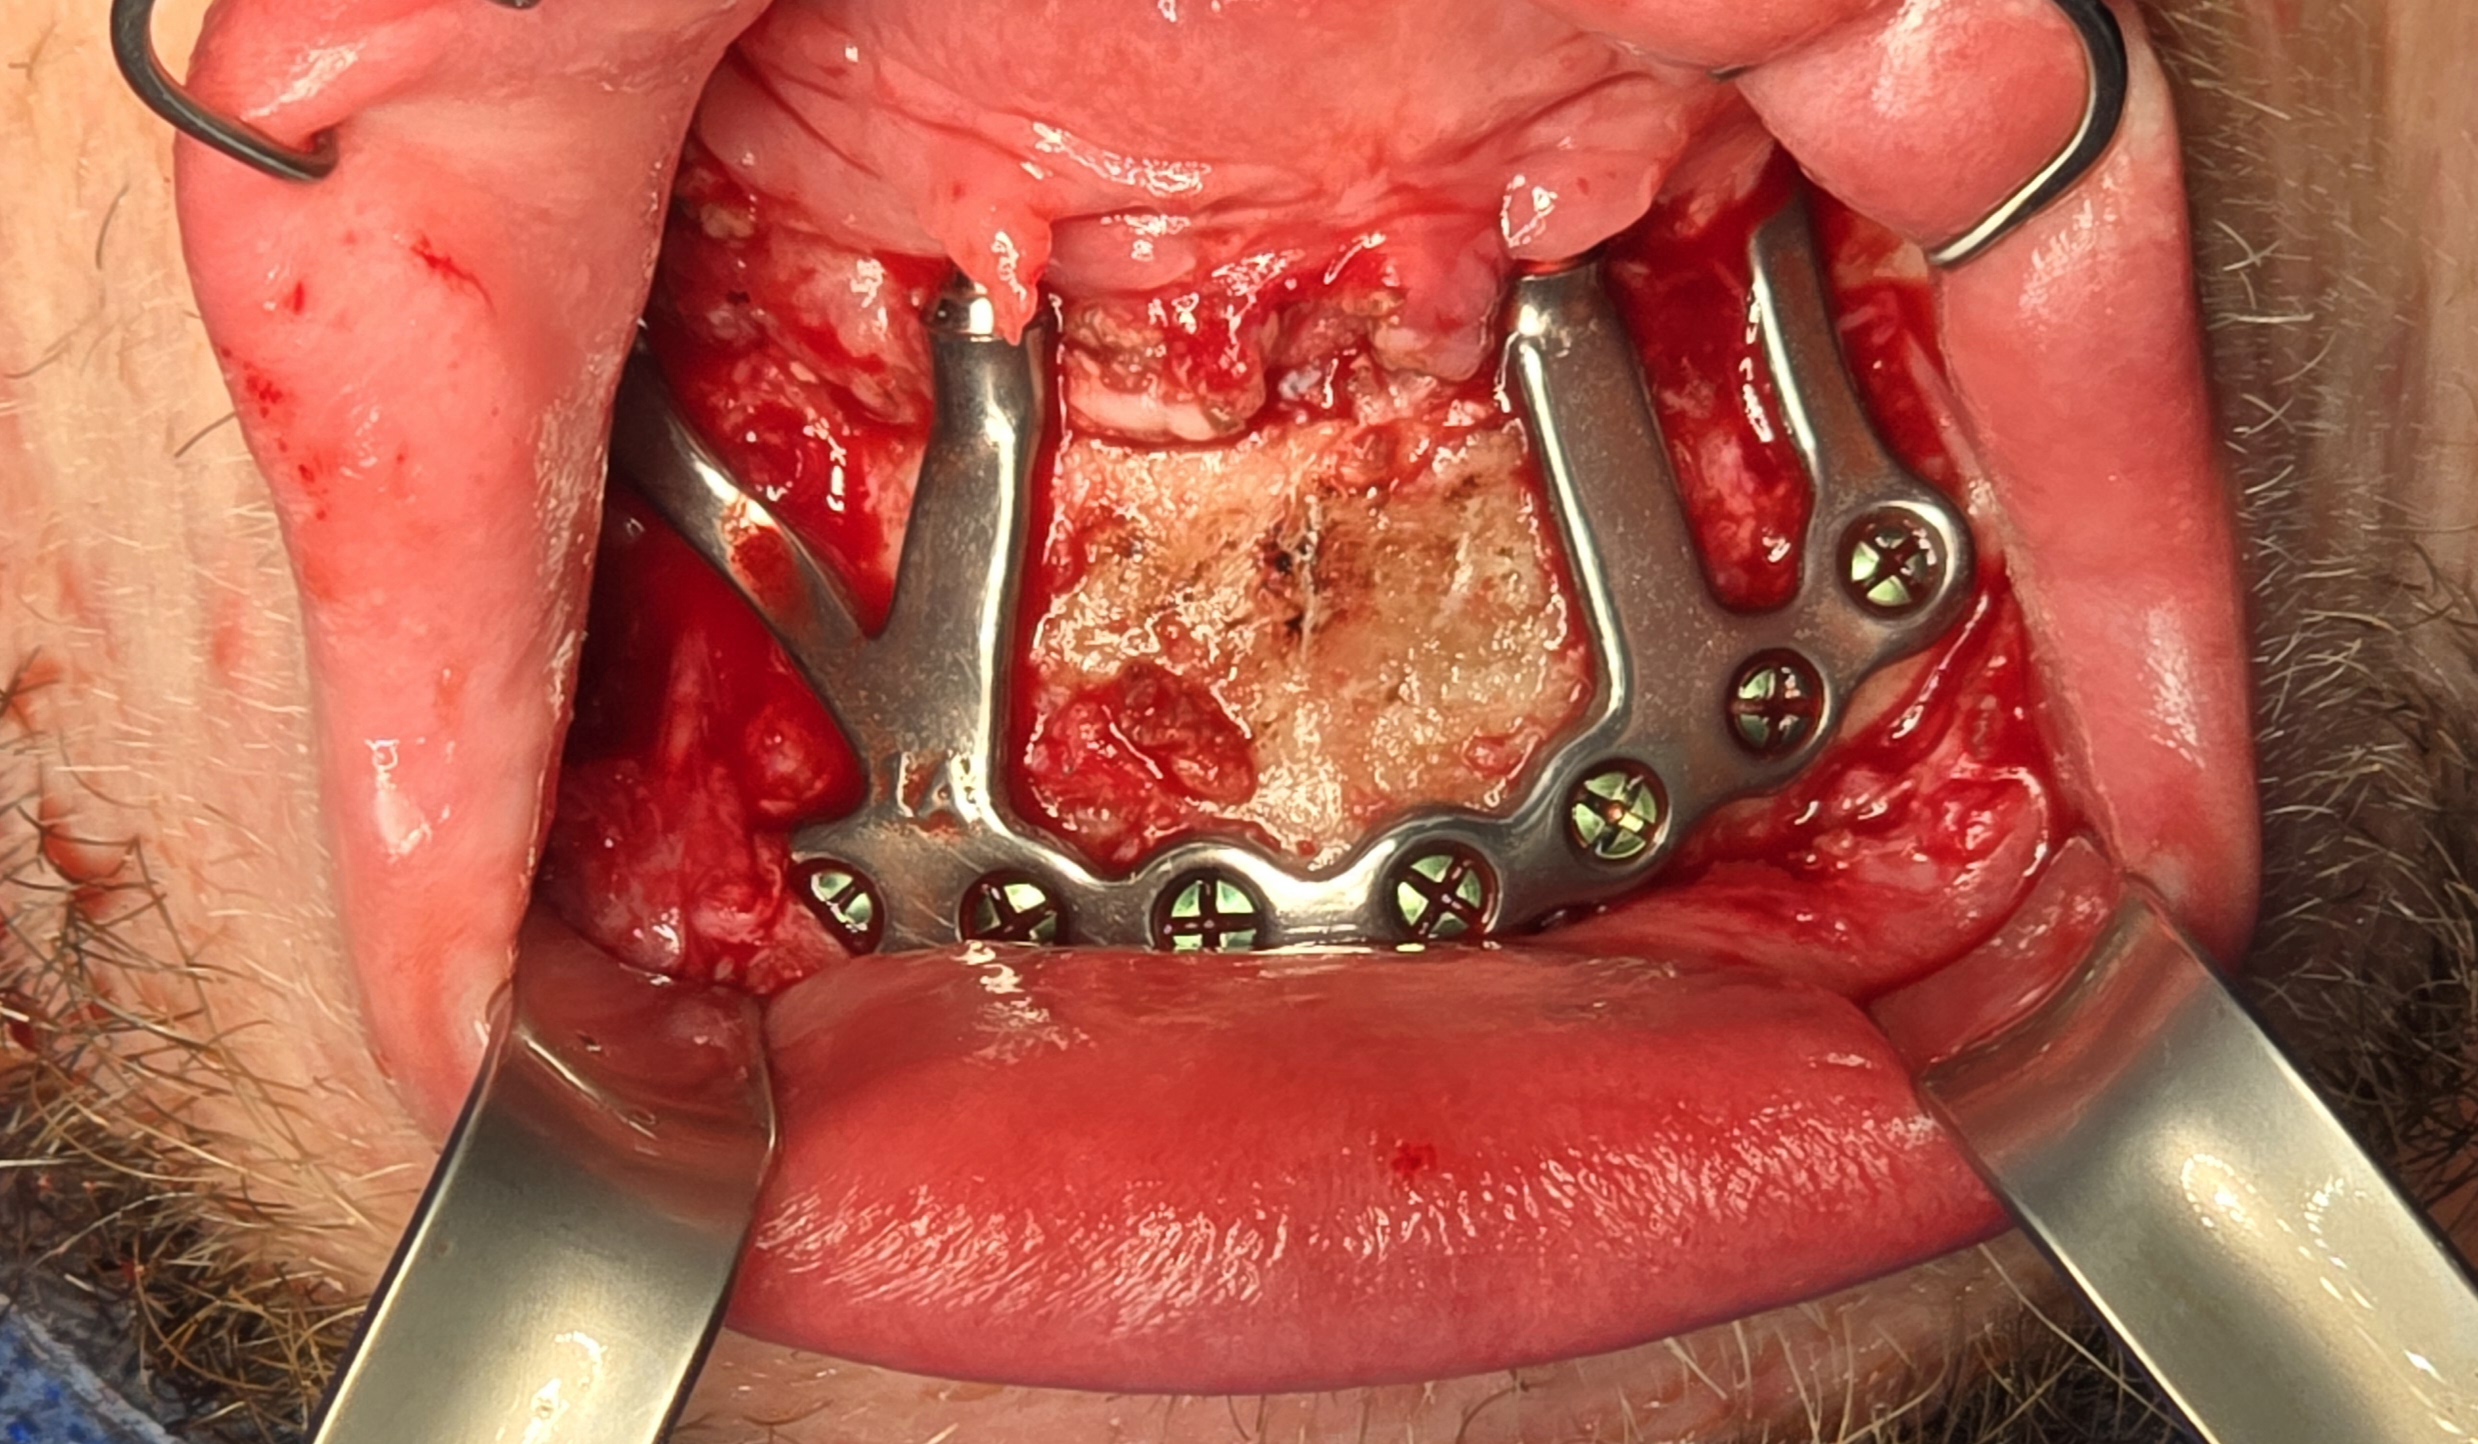

Under general anesthesia in an operating room setting, a crestal incision with bilateral releasing incisions was made on the mandible. Subperiosteal dissection extended to the inferior border of the mandible while preserving both mental nerves. A CAD-CAM bone reduction guide was rigidly fixated and used to perform alveoloplasty and predict fixation sites.

The custom titanium framework was trial seated and adapted accurately.

Due to the patient’s trismus, a transbuccal trocar system was used bilaterally to access posterior fixation sites, a technique commonly used in limited access mandibular fixation [17]. Locking screws were. placed under copious irrigation to achieve rigid stabilization (Fig 8).

A custom occlusal splint confirmed mount and prosthetic space. The site was closed with resorbable sutures intraorally and plain gut at trocar sites. Recovery was uneventful, and the patient progressed to prosthetic rehabilitation (Figs 9 and 10).